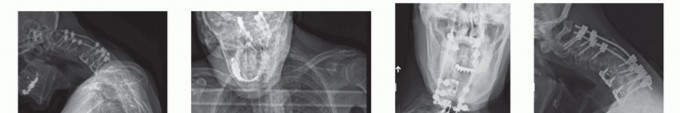

DEFINITION The precise definition of cervical kyphosis is not clearly described. Normal alignment from C2 to …

DEFINITION In recent years, the number of patients undergoing cervical spine surgery has risen dramatically. …